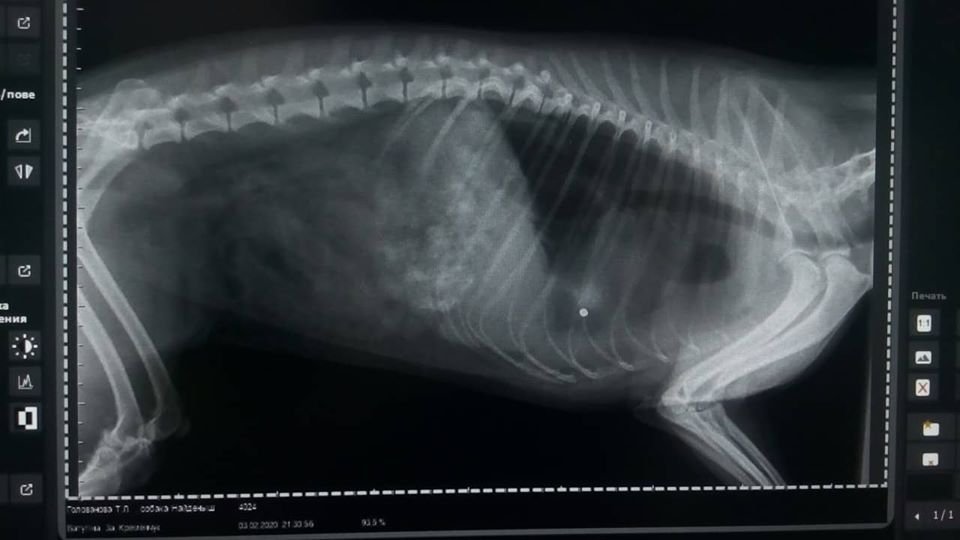

Вчора кременчужанка на руках до «Спецсервісу» принесла пораненого собаку. Як повідомила на своїй сторінці начальниця служби відлову комунального підприємства «Спецсервіс» Марина Кожушко, як це сталося ніхто не бачив.